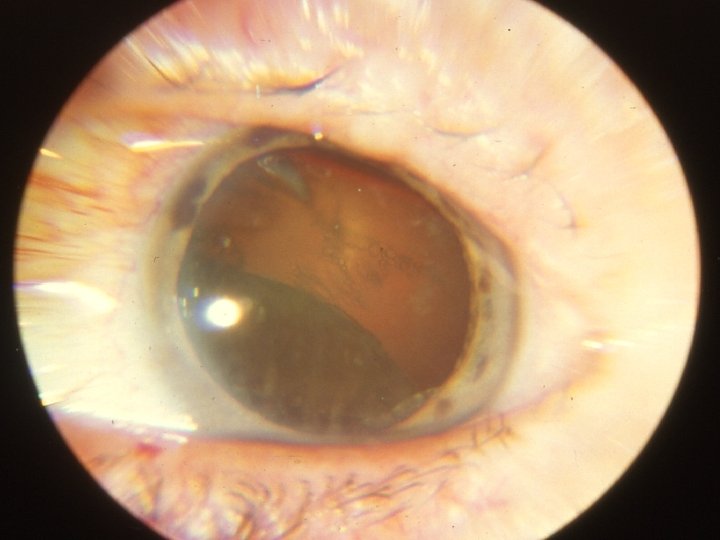

Traumatologie et Brûlures oculaires 2 - Contusions du globe Le syndrôme traumatique du SA Cataracte traumatique Fait suite à un traumatisme violent même sans plaie oculaire Évolution variable, atteinte postérieure en rosace Subluxation Luxation antérieure ou postérieure Consultation pour bilan d’autres lésions associées

Traumatologie et Brûlures oculaires 2 - Contusions du globe Le syndrôme traumatique du SA Troubles du tonus oculaire Hypotonie: par sidération du corps ciliaire mais !! Rupture postérieure (BAV) Hypertonie: céphalées, vomissements Précoce , aigüe, +/- hyphéma Tardive, chronique, ttt difficile, glaucome traumatique